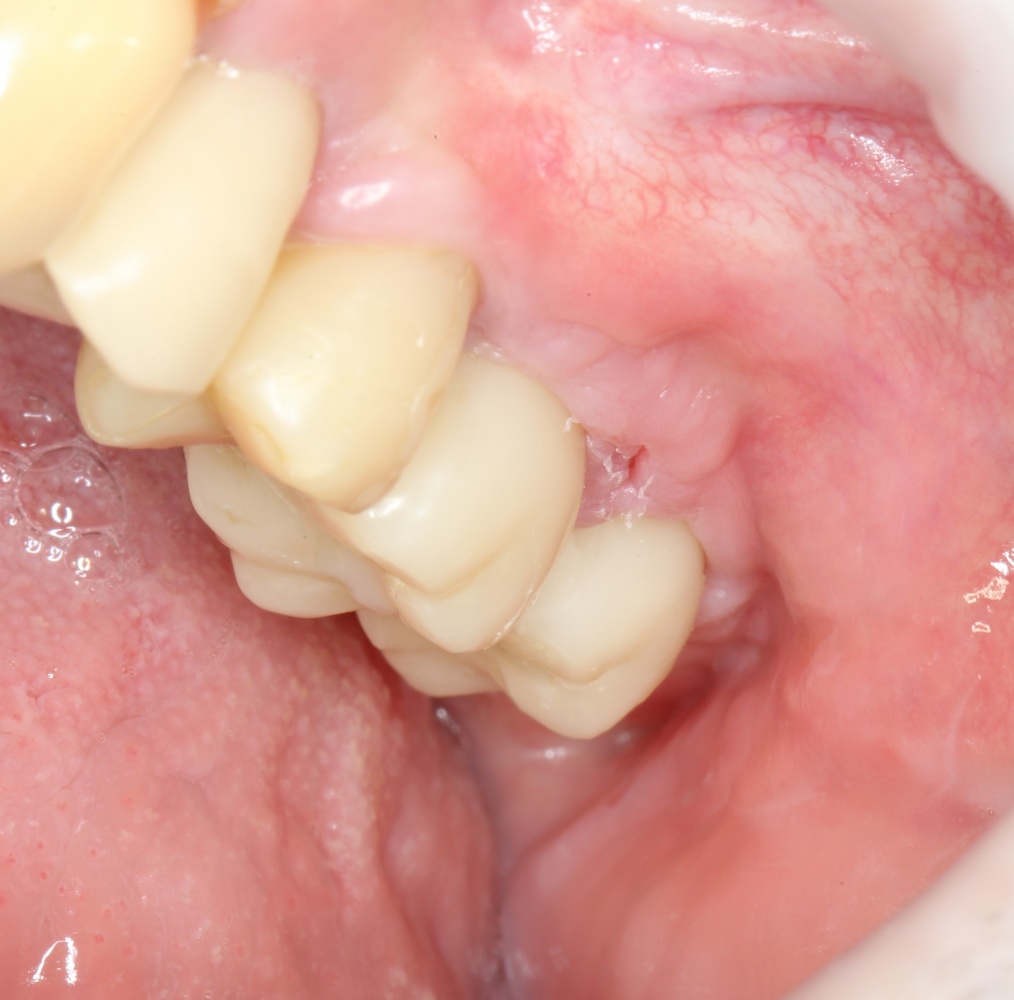

Через пару недель область, где мы провели уже две операции, выглядит примерно так:

или, если снять формирователи:

Можно передавать пациента ортопеду для временного протезирования. Что он и делает:

Важным условием гарантийных обязательств в нашей клинике являются профилактические осмотры, которые проводятся один или два раза в год (см. Гарантии и Долгосрочное наблюдение). Через полтора года после протезирования, при очередном осмотре мы сделали фотографии и снимок: